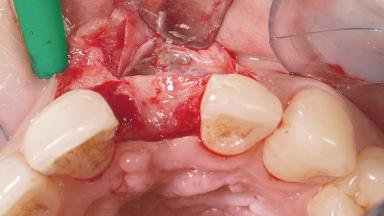

A 30-year-old female patient had lost tooth 21 and was referred to our clinic for consultation and treatment. Due to advanced apical infection, tooth 21 had been extracted two months earlier at another clinic and an acrylic-resin tooth had been bonded to the adjacent teeth. The patient desired implant treatment to avoid any damage to the adjacent natural teeth. While the patient had no history of any systemic disorder, she was a heavy smoker and exhibited medium to advanced periodontitis in the entire jaw. After the initial treatment to achieve a pocket probing depth of less than 4 mm and no bleeding on probing, a decrease in the height of the papillae mesial and distal to the extraction site and overall gingival recession were observed.

Soft Tissue Grafting Simultaneous

Soft Tissue Anatomy Intact Defective

Soft Tissue Contour and Volume Slightly compromised